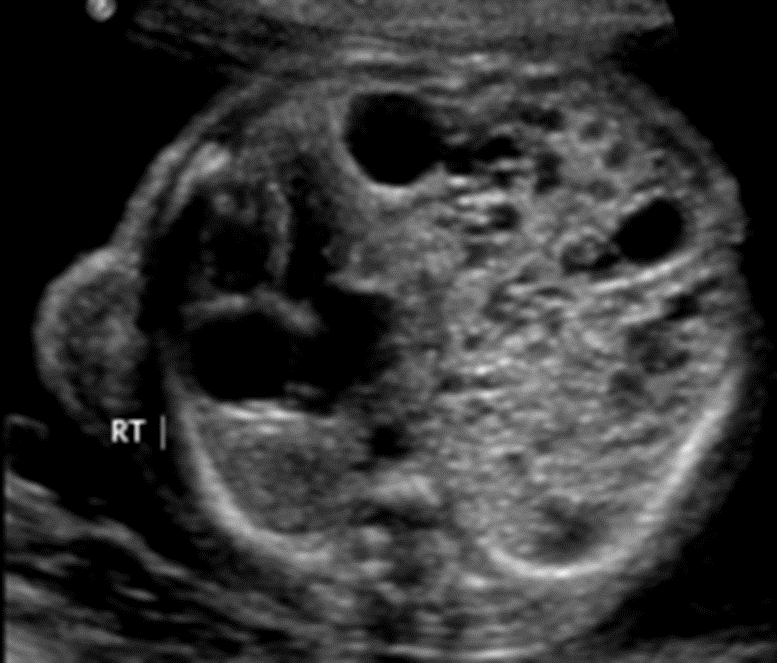

A level 2 fetal ultrasound shows mediastinal shift as seen below.

Name what is causing the shift and what index

is used to prognosticate the risk of hydrops fetalis.

What is a Congenital Pulmonary Airway Malformation (CPAM)?

What is a CPAM Volume Ratio (CVR)?

>1.6 increases risk of hydrops